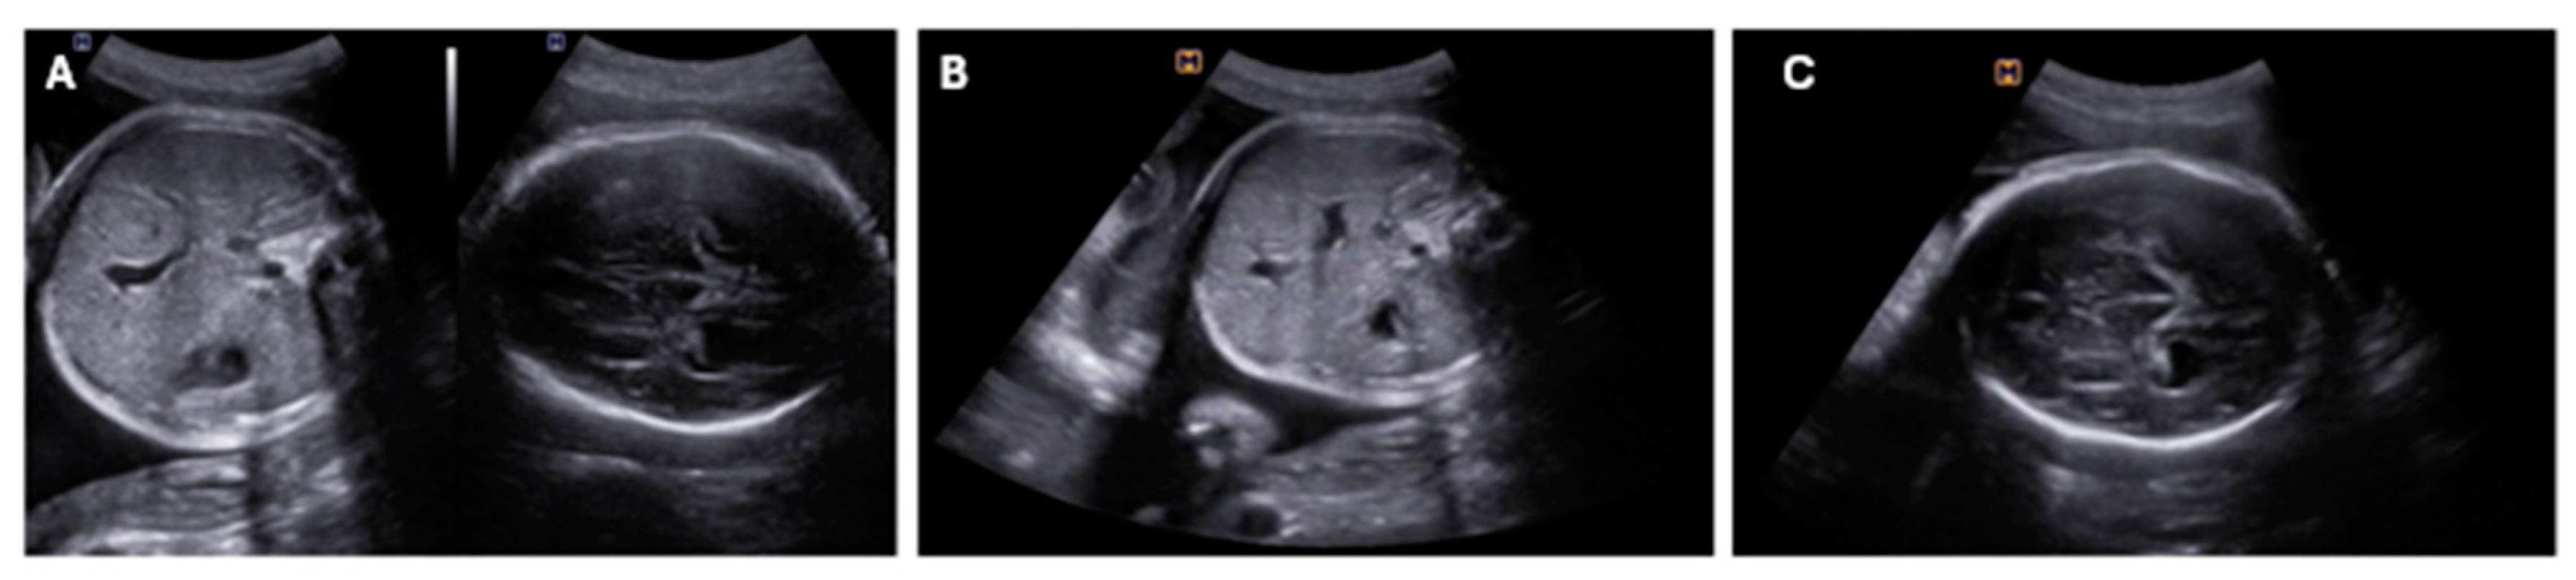

| Fetal | Cerebral ventriculomegaly Cardiomyopathy with ventricular dysfunction Polyhydramnios Ascites Pericardial and pleural effusions Decreased fetal movements Multi-visceral failure Intrauterine fetal death |